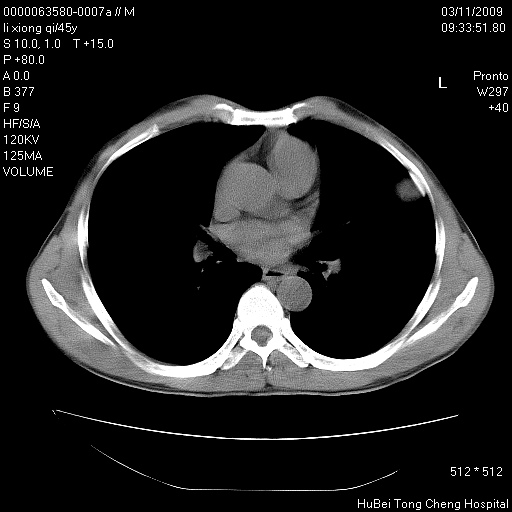

患者 男,45岁。胸痛,咳嗽伴痰中带血1月余。

临床诊断:肺结核?

胸部ct轴位平扫(层厚10mm,螺距1.5,重建间隔10mm),图像如下: